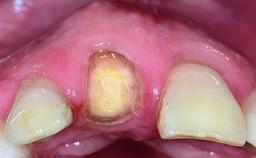

A 36-year-old male patient with a compromised maxillary central incisor was referred by his general dentist for consultation. The patient’s chief complaints were the gradual debonding of a temporary crown on the right central incisor and unsatisfactory esthetics due to an increasing diastema between the right central and lateral incisors. The patient reported a traumatic event some years previously, when a crown had been placed after root-canal treatment. The referring dentist wanted to provide a new crown restoration, but was concerned about the condition of the residual root. Anamnesis was negative for any other dental or periodontal pathology in the remaining dentition. The patient reported taking no medications: He was a smoker (10 to 15 cigs/day) and had realistic esthetic expectations.